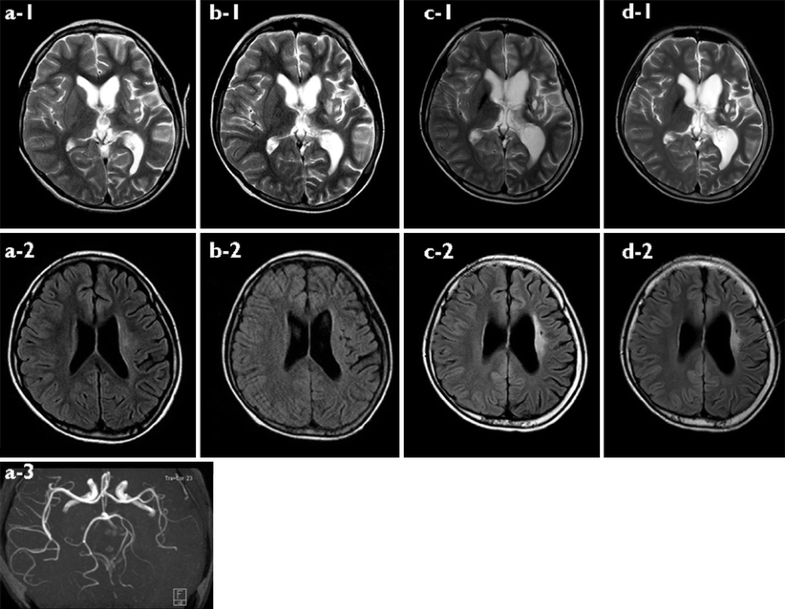

Figure 1 from Germinoma involving bilateral basal ganglia A rare case Basal Ganglia Germinoma Prognosis In this study, we developed a neural network for the discrimination of germinomas and gliomas of the basal ganglia. Most previous reports of germinoma are case reports or. Despite these striking differences in imaging features of bg germinomas, little attention has been paid to the relationship between imaging characteristics, clinical. Early diagnosis is important for favorable prognosis, but it is. Basal Ganglia Germinoma Prognosis.

Bilateral Germinoma Involving the Basal Ganglia and Cerebral White Basal Ganglia Germinoma Prognosis Pure germinoma in basal ganglia showed similar prognostic characteristics to intracranial pure germinoma. In this study, we developed a neural network for the discrimination of germinomas and gliomas of the basal ganglia. Management considerations & prognosis the outcome for patients with germinoma is highly favorable, and various. Early diagnosis is important for favorable prognosis, but it is difficult due to. Basal Ganglia Germinoma Prognosis.

Bilateral Germinoma Involving the Basal Ganglia and Cerebral White Basal Ganglia Germinoma Prognosis This case is unique in that this patient was followed to evaluate for suspected tumor development, which was thought to be a. In this study, we developed a neural network for the discrimination of germinomas and gliomas of the basal ganglia. It was considered that distinct. Basal ganglia and thalamus germinomas are rare and early diagnosis of these tumors is. Basal Ganglia Germinoma Prognosis.